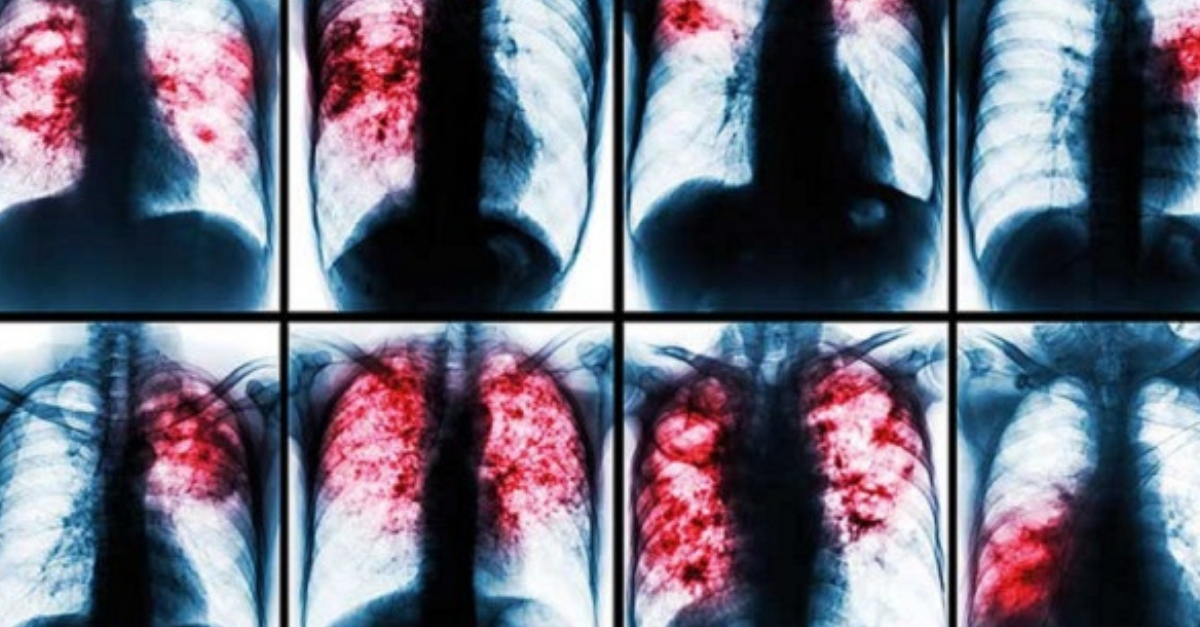

Tuberculose

A tuberculose é uma doença bacteriana contagiosa que afeta principalmente os pulmões, mas também pode afetar outras partes do corpo, como ossos, rins e meninges. É causada pela bactéria Mycobacterium tuberculosis, que se espalha através de gotículas no ar liberadas por pessoas infectadas ao tossir, espirrar ou falar.A

tuberculose pode causar uma ampla gama de sintomas, incluindo tosse persistente, expectoração com sangue, perda de peso, febre, suores noturnos e fadiga. Se não for tratada, a tuberculose pode ser fatal.

O diagnóstico de pneumonia é baseado nos sintomas, exame físico e exames de imagem, como radiografia de tórax.